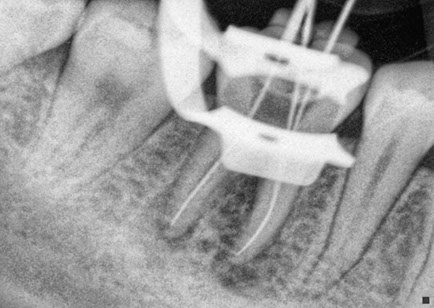

Durante un procedimiento de conducto radicular, o endodoncia el nervio y la pulpa se eliminan y el interior del diente se limpia, se empasta la raíz con los materiales correspondientes y se procede a la reconstrucción de la corona dental, todo éste tratamiento se realiza habiendo aplicado anestesia local en la zona afectada, la misma anestesia que se utiliza para un simple empaste o una extracción.

La endodoncia le da más tiempo de vida útil a su pieza dental, en Dental Evolution Cancún le recomendamos evitar la extracción realizándose este procedimiento que garantizamos será sin dolor, gracias a la tecnología de vanguardia con la que contamos, instrumental rotatorio, sistema de ultrasonido, y a nuestra “radiografía digital” la cual juega un papel crucial en el procedimiento de endodoncia, además de que usted estará atendido con la calidez, calidad humana y profesionalismo que caracteriza a nuestro experto equipo de dentistas especializados que le apoyaran en todo momento.